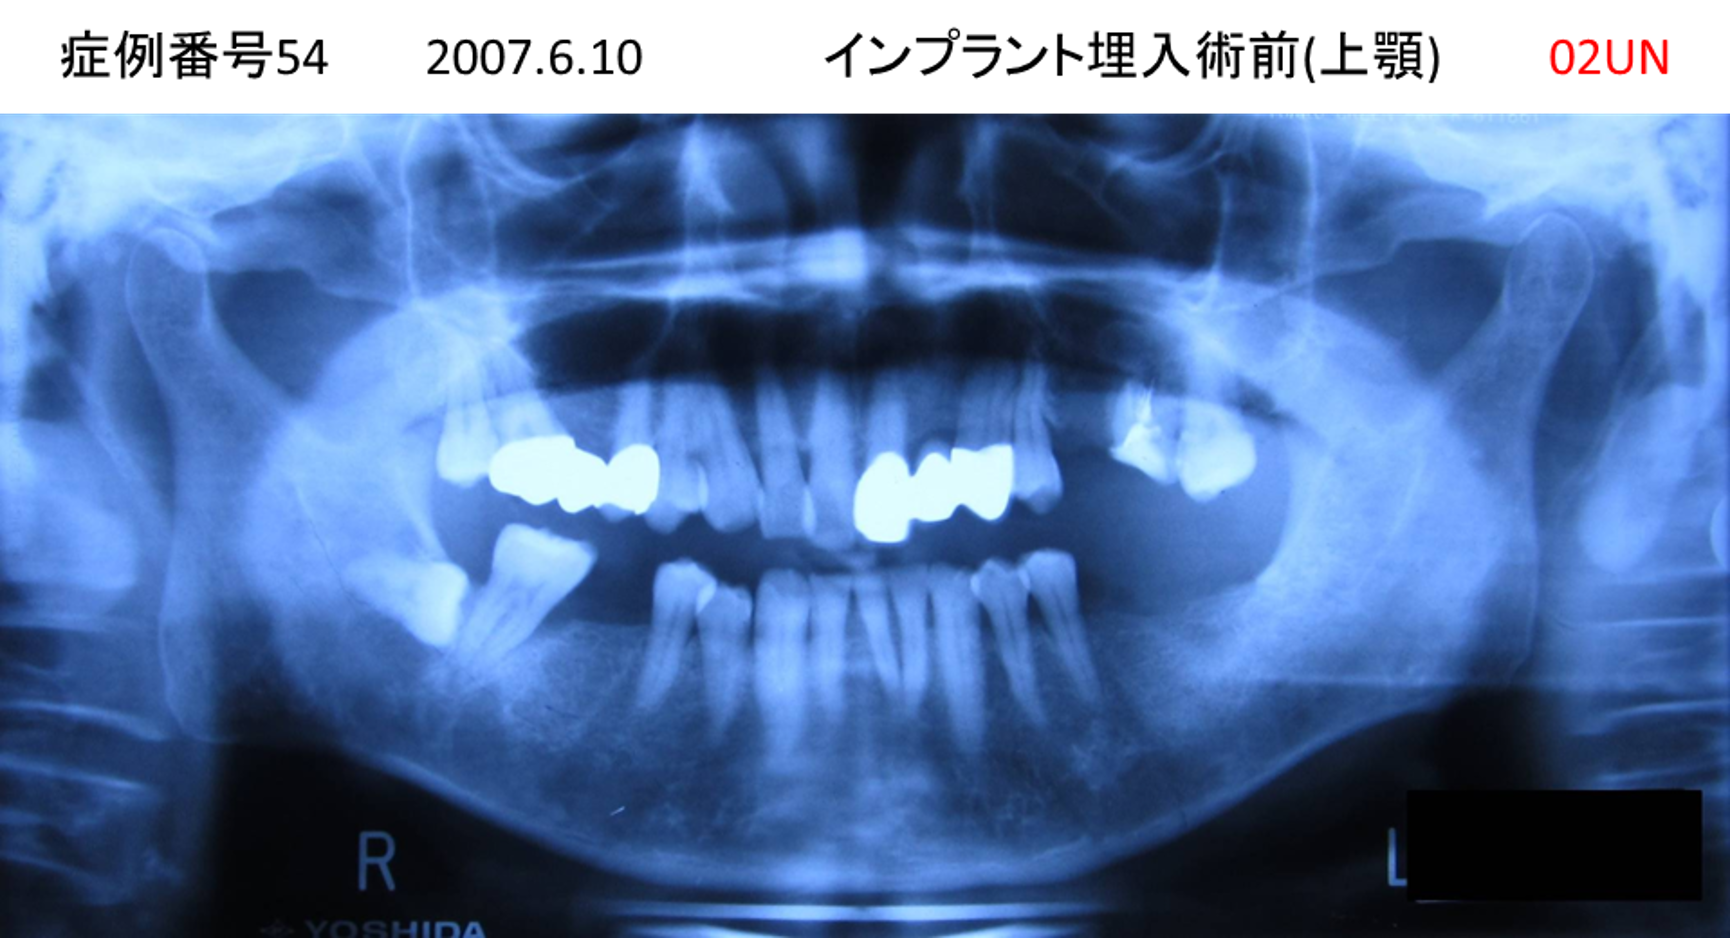

ご飯を美味しく食べたい/人前で笑えるようになりたい患者様のインプラント症例

| 治療名称 |

インプラント |

| 治療費用 |

480万円+税 |

| 治療期間 |

6か月 |

| 患者さんの症状(主訴) |

おいしいご飯が食べられるようになりたい 人前で笑えるようになりたい |

| 治療内容 |

サイナスリフト 抜歯即時インプラント |

| 治療結果 |

何でも食べられるようになった 人前で大口を開けて笑えるようになった |

| 治療の注意点(リスク/副作用) |

インプラントが壊れた場合は再治療が必要 |